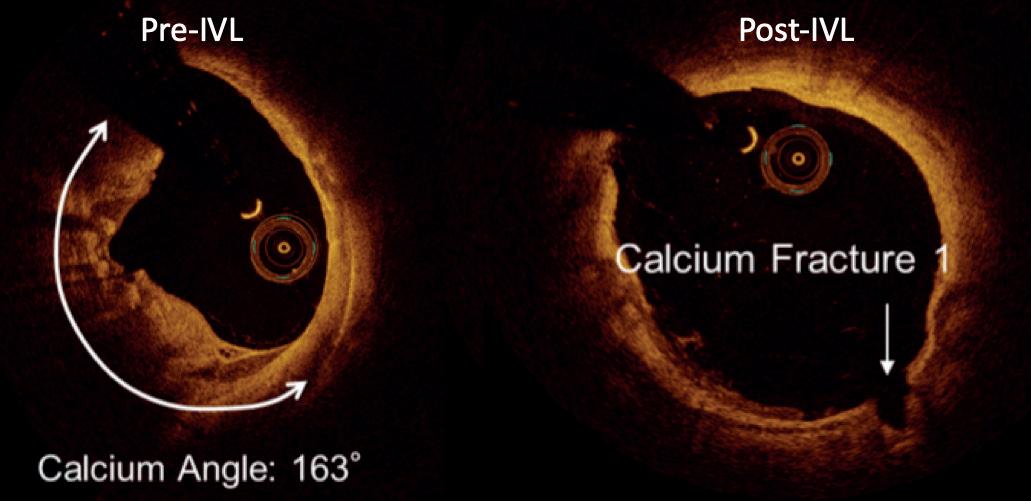

tomography (OCT). The high spatial resolution of OCT clearly demonstrates controlled microfractures and dissections in both the intimal and medial layers of calcium without the uncontrolled spiral dissections often seen after plain balloon angioplasty (Figure 1).

The phenomenon of low pressure dilatation of calcified vessels is a frequent and impressive finding after IVL. Confirmation of this controlled fracturing of vascular calcification has been obtained in preclinical cadaveric micro-CT studies. Clinically, this has also been demonstrated on intravascular ultrasound (IVUS) and optical coherence

Figure 1. OCT pre- and post-IVL